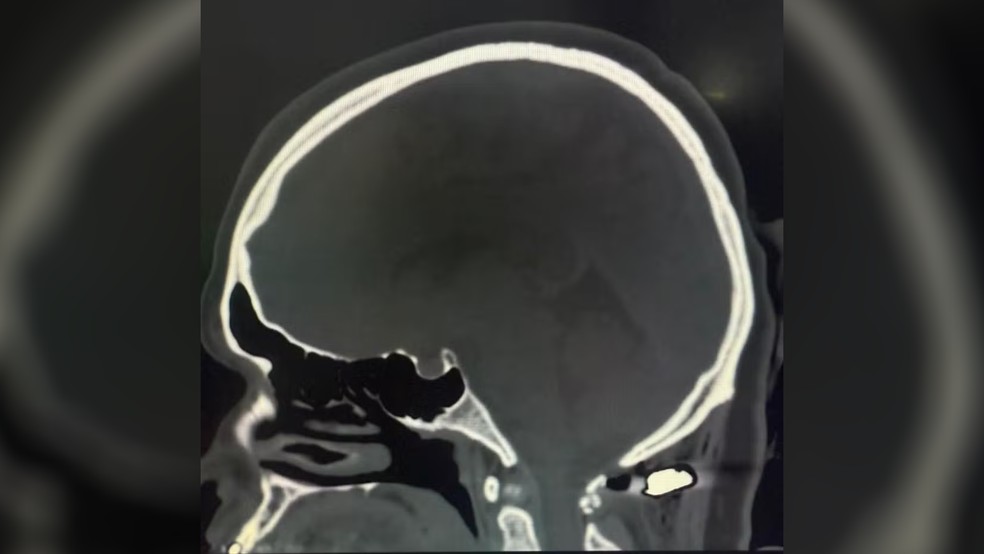

Juliete Pires dos Santos Scrok, de 36 anos, sobreviveu a um tiro na nuca e escapou de ficar tetraplégica por apenas 4 milímetros, segundo o neurocirurgião Felipe Salvagni Pereira, que realizou o atendimento no Hospital Angelina Caron, em Campina Grande do Sul.

O médico explicou que o projétil ficou a poucos milímetros da medula cervical — região que, se atingida, poderia causar morte ou tetraplegia. “Foi um milagre”, afirmou o especialista. Juliete passou por cirurgia e segue se recuperando bem.